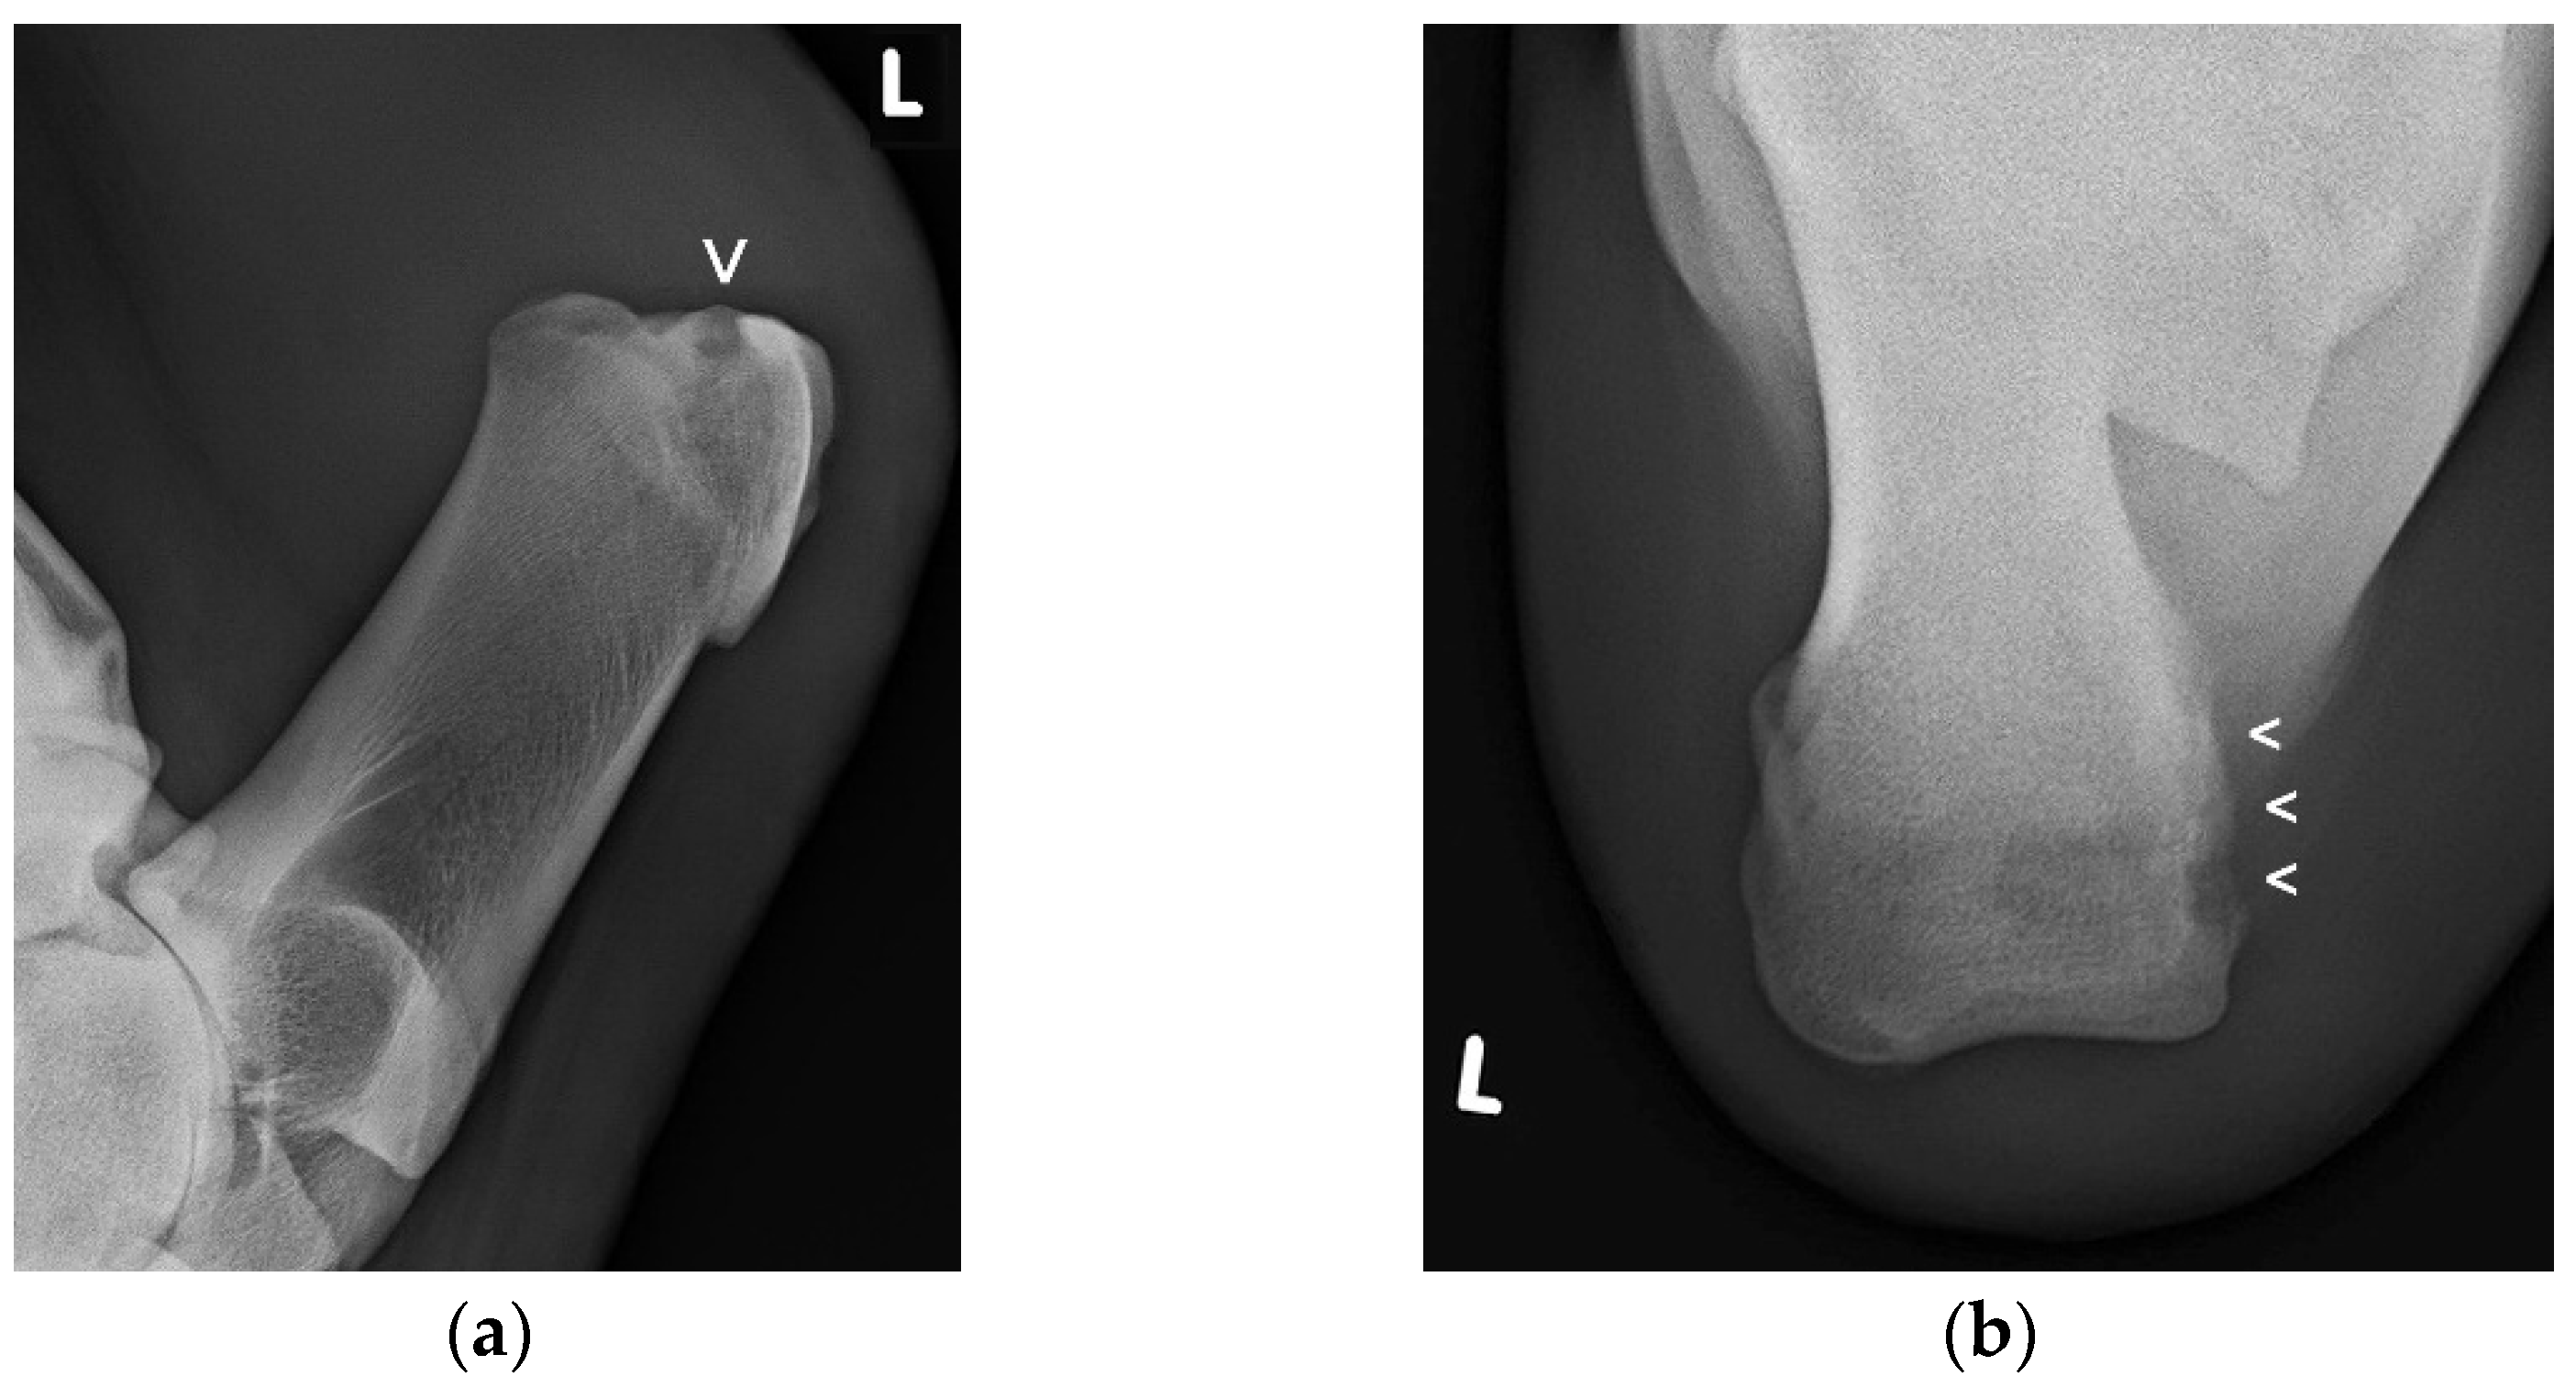

Ultrasonographic examination was conducted in all 29 patients and the following was identified: an inflammatory, heterogenous effusion in all 33 cases of bursitis (100%), gas pockets within the bursal cavity in 15 cases (45.5%), bone lesions at the CT in 16 cases (48.5%) (Figure 2a–c), and lesions of the SDFT with loss of echogenicity and loss of parallel fiber arrangement leading to the diagnosis of partial and total tendon necrosis/rupture in three cases (9.1%), respectively. All three cattle with SDFT lesions had concurrent bone osteolysis of CT.

Figure 2. Longitudinal sonogram (5 MHz linear) of the CT region at the insertion site of the Achilles tendon (a), and transverse sonograms (5 MHz linear) of the plantaromedial (b) and medial aspect (c) of the proximal CT showing a septic purulent bursal effusion (a) and bone involvement (infection) in this cow; the bursal cavity (BU) is highly enlarged due to the presence of heterogeneous hypoechoic exudate with an anechoic, partly hypoechoic to echoic and “snow-flurry-like” appearance, the latter in particular at the medial aspect of the bursal cavity with flow phenomena (b,c), indicative of a purulent exudate. Due to the severe effusion, the superficial digital flexor tendon (SDFT) is displaced plantarily, as is the bursal capsule (C). The contour of the CT appears normal at the insertion site of the lateral (LGT) and medial gastrocnemius tendons (MGT) (a), but highly irregular (white arrows) at the plantaromedial (b) and, in particular, at the medial aspect of the CT (c) indicating extensive osteolysis.